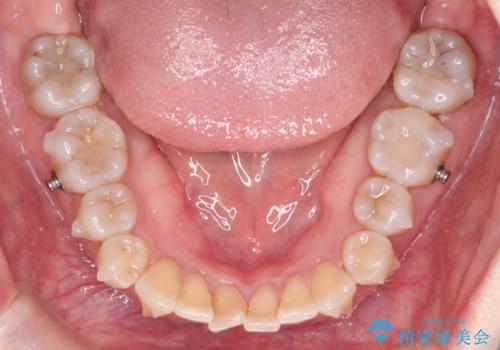

- 前歯の凸凹を主訴に来院されました。

インビザライン にて治療を行い、歯並びが綺麗になったと満足していただきました。

前歯のガタガタの量が多かったため、IPR(歯のサイズを小さくするための処置)を行なって治療しました。